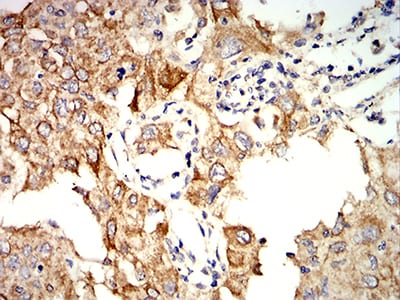

IHC 1/200 - 1/1000 Human,Monkey

The KRT10 antibody is a tool used to detect keratin 10 (KRT10), a type I intermediate filament protein expressed in the suprabasal layers of stratified epithelia, particularly the epidermis. KRT10 pairs with keratin 1 (KRT1) to form a structural framework essential for epidermal integrity and barrier function. It plays a critical role in terminal differentiation of keratinocytes, contributing to skin’s mechanical resilience. Mutations in the *KRT10* gene are linked to genetic disorders like epidermolytic ichthyosis (EI), characterized by skin fragility and hyperkeratosis. In research, KRT10 antibodies are widely employed in immunohistochemistry, immunofluorescence, and Western blotting to study epidermal differentiation, skin pathology, and cancer. They help identify aberrant keratin expression in squamous cell carcinomas, psoriasis, or wound-healing models. Clinically, these antibodies aid in diagnosing EI and differentiating it from other ichthyoses. Additionally, KRT10 serves as a marker for terminally differentiated keratinocytes, making its antibody valuable in studying epithelial-mesenchymal transitions or drug effects on skin models. Its specificity ensures reliable detection of KRT10’s distribution and expression levels in both normal and diseased tissues.